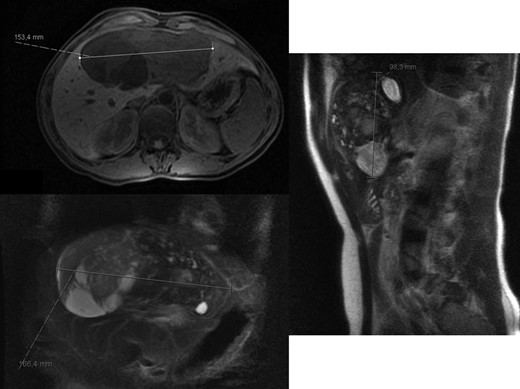

A 26-year-old woman, with past medical history of removal of hemangiopericytoma of the right leg, was referred to our Hepatobiliary Unit due to a liver tumor that was discovered on abdominal-pelvic computed tomography (CT) scan, performed after complaints of epigastric pain. CT scan (Fig. 1) showed a voluminous, heterogeneous, hypervascular mass, occupying segments 4, 5 and 8, with 19 cm in diameter, as well as suspicious lesion on left iliac bone suggestive of solitary fibrous tumor metastasis.

Abdomino-pelvic computed tomography (AP-CT) – voluminous heterogeneous liver mass in segments 4, 5 and 8 with 19 cm in diameter.